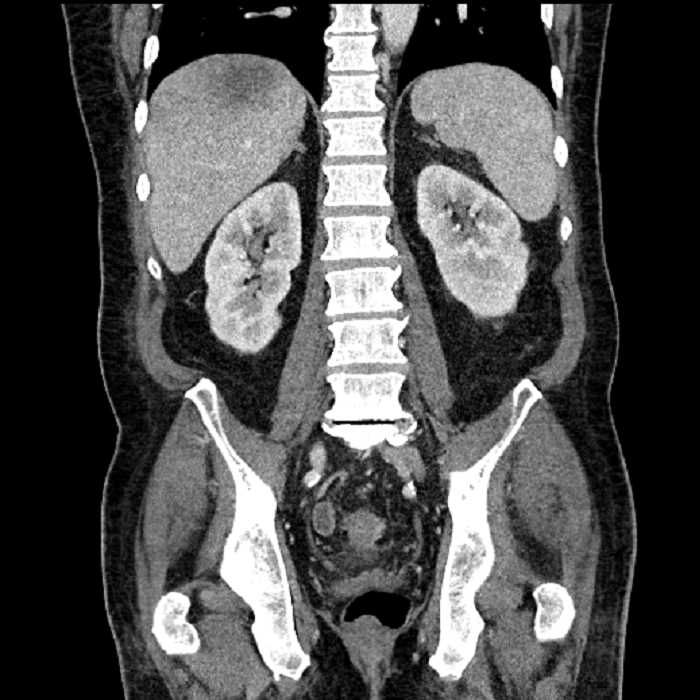

• Mild mural thickening of a segment of the sigmoid colon with adjacent fat stranding and a 1.5 cm fluid and gas collection along the tip of an inflamed diverticulum

• Loss of the normal fat plane between this collection and adjacent loops of small bowel, which demonstrate mural thickening

• No bowel obstruction

Acute sigmoid diverticulitis complicated by a small contained perforation and a large abscess in the right hepatic lobe. Additional small subcapsular abscesses along the anterior margin of the left hepatic lobe.

Additionally, loss of the normal fat plane between the peridiverticular collection and adjacent thickened loops of small bowel raises the potential for an enterocolonic fistula.

Hepatic abscess showing the double target sign with low density internally surrounded by a thin inner enhancing rim (red arrow) and ill-defined outer low density rim (yellow arrow). Blue arrow indicates an internal septation. Red arrows: additional smaller subcapsular abscesses. Red arrow: focal contained perforation associated with diverticulitis.